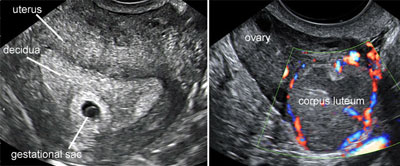

The gestational sac and the corpus luteum

Legend:The gestational sac and the corpus luteum

The corpus luteum

Legend:The corpus luteum